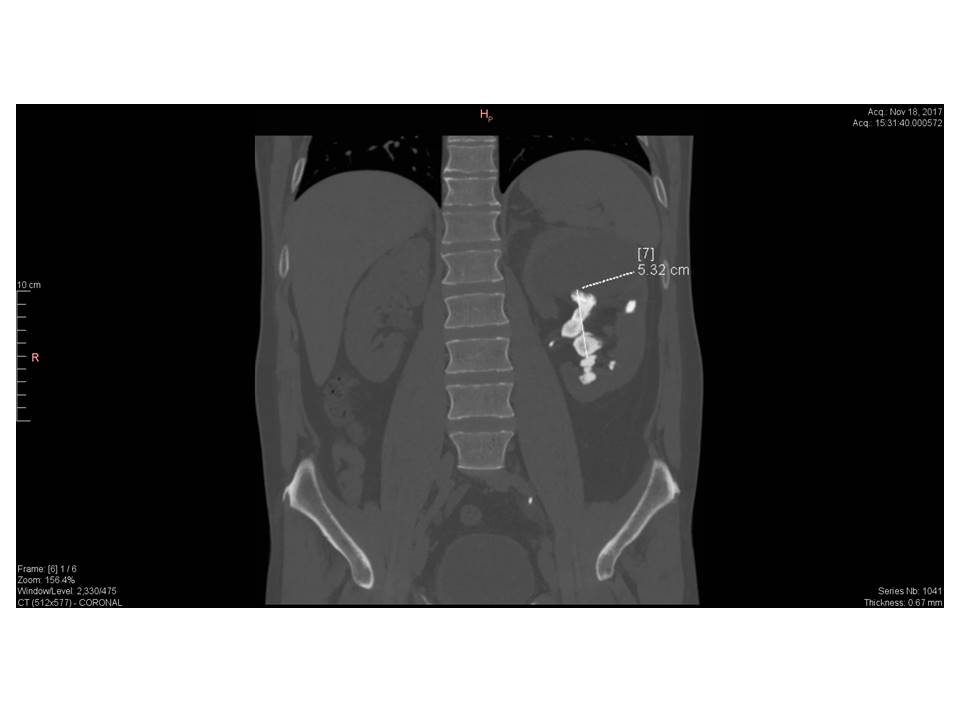

Staghorn calculi, also sometimes called coral calculi, are renal calculi that obtain their characteristic shape by forming a cast of the renal pelvis and calyces, thus resembling the horns of a stag.

Staghorn calculi are the result of recurrent infection and are thus more commonly encountered in women 6, those with renal tract anomalies, reflux, spinal cord injuries, neurogenic bladder or ileal ureteral diversion.

The majority of staghorn calculi are symptomatic, presenting with fever, haematuria, flank pain and potentially septicaemia and abscess formation.